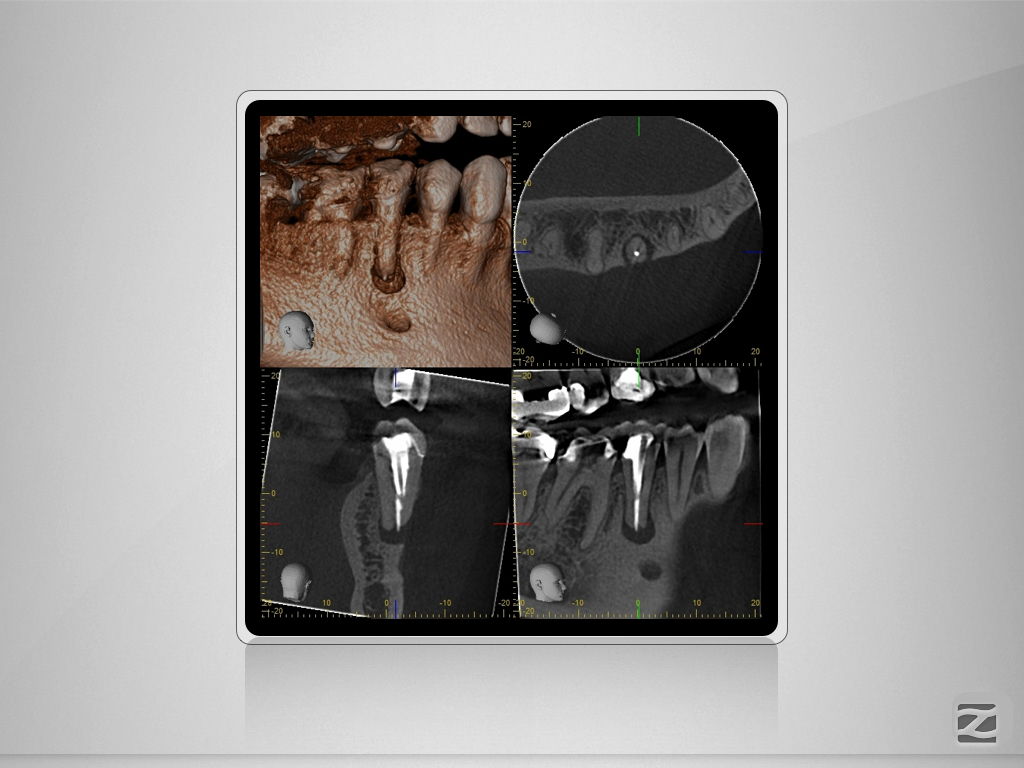

45D.003

1024 × 768

2D vs. 3D (XXXI)